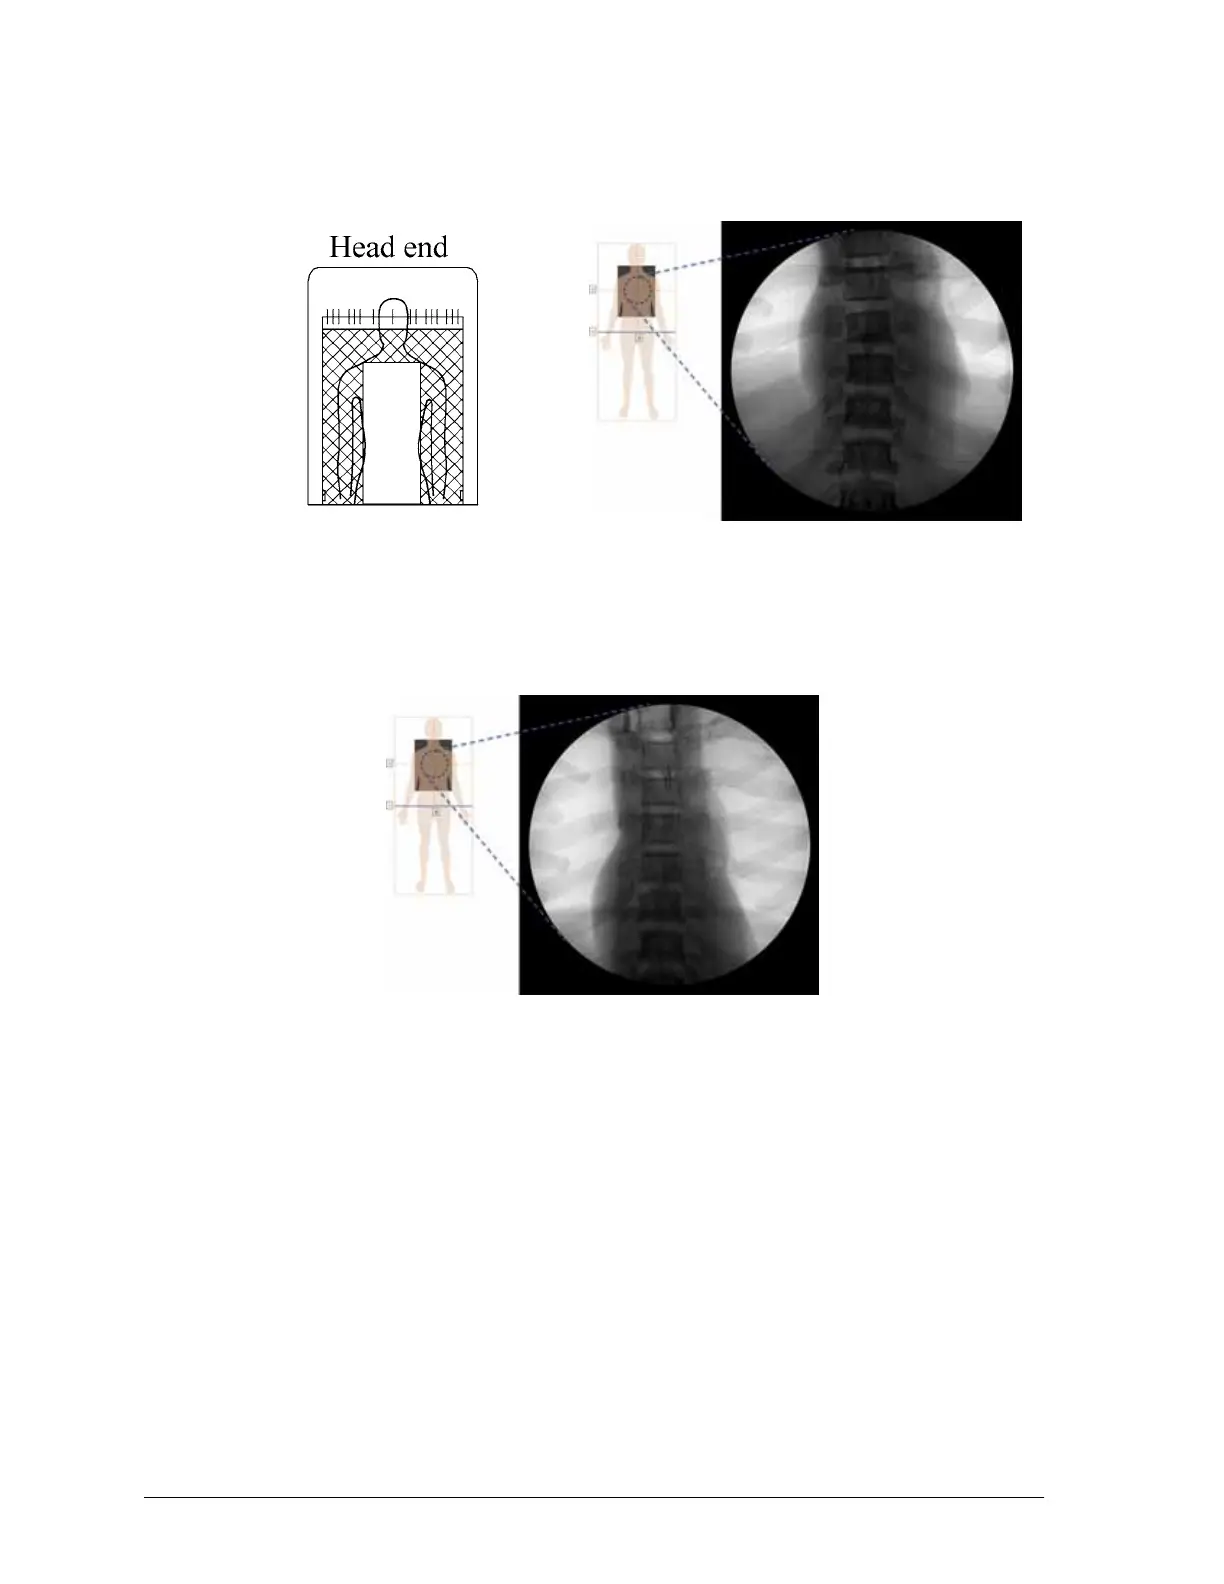

Progressa™ Therapy and Pulmonary mattress artifact locations

Prevention mattress artifact locations

Progressa™ Prevention mattress shown

Progressa™ Pulmonary mattress shown

(artifacts can include metal coil and non-metal tubing and fittings)

Artifact locations